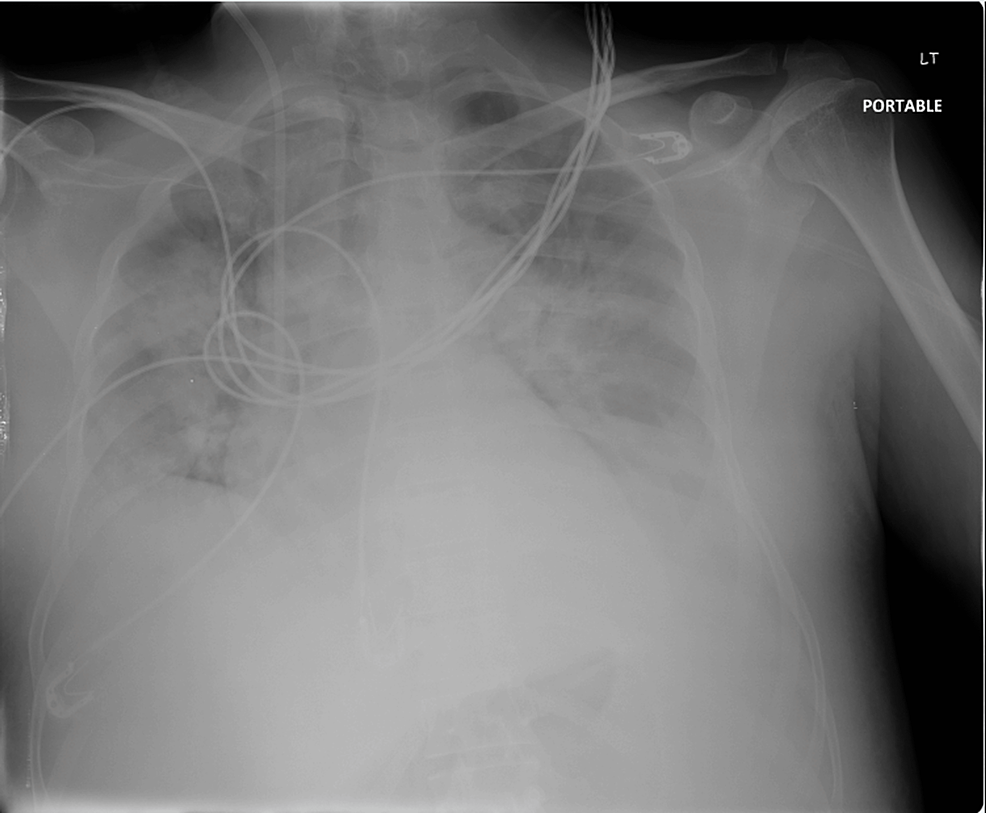

Cureus Impending Cardiac Tamponade as the Initial Manifestation of

from www.cureus.com